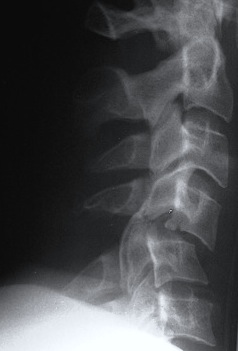

Unilateral facet joint dislocation on xray - 25% subluxation on lateral X-ray (<50%)

>50% forward subluxation